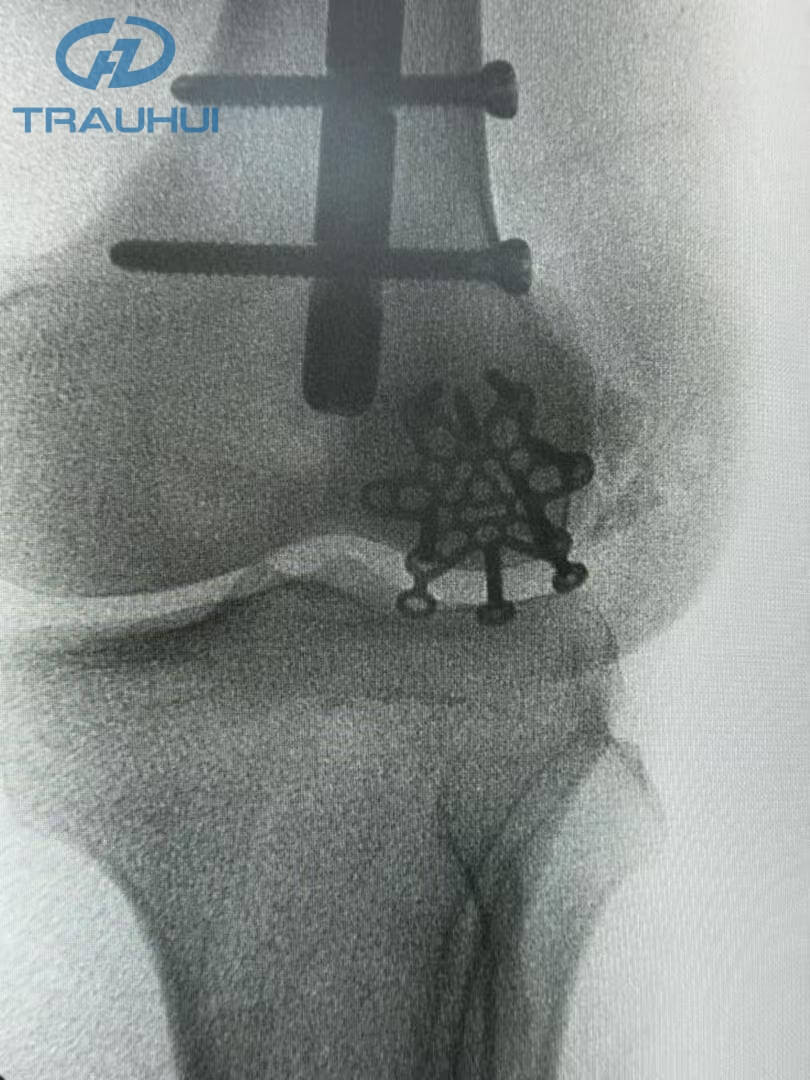

Anterior Patella Plates3.jpg

Figure 4: X-Ray

The post-surgery X-ray confirmed what the surgeon felt in the OR: unmatched stability. By replacing the "settling" nature of cerclage wires with the rigid, anatomical fixation of our new plate, the patient is now positioned for a faster rehabilitation with a reduced risk of hardware failure.